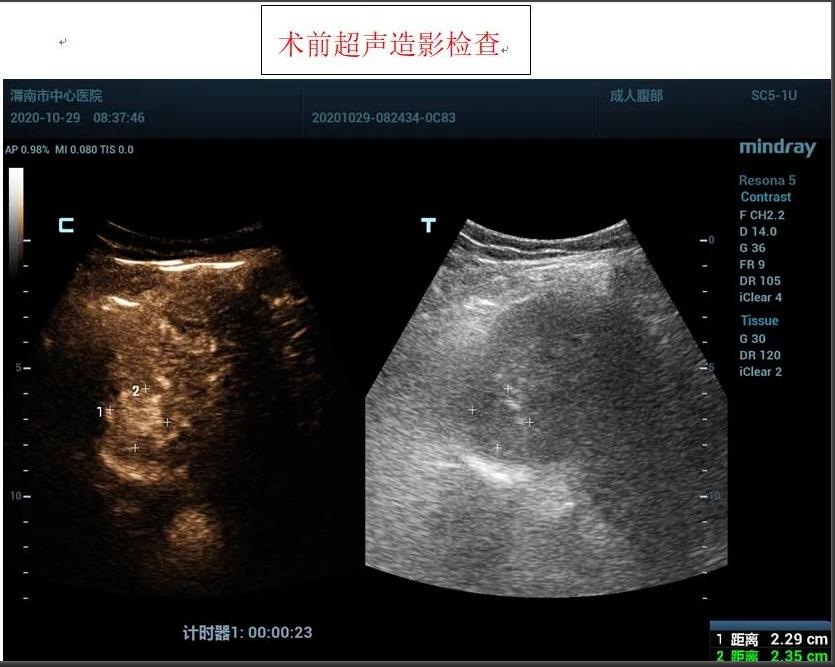

患者女性,71岁,因“糖尿病、肝硬化”在外院进行治疗,住院前进行常规检查,发现肝脏占位性病变,为进一步诊治前来我院,入住感染性疾病科,为进一步明确肝脏肿瘤性质,为患者进行超声造影检查,根据超声造影血流灌注情况,提示肝脏右前叶上段肝细胞癌可能。

患者肿瘤较小且位置较深,紧贴膈肌,且患者伴有冠心病、糖尿病等基础性疾病,感染科李红兵主任在充分评估患者状况后,与超声科刘晓晖主任进行细致讨论,决定对患者行超声引导下微波消融术,因病灶位置特殊,为减少手术风险,特邀西京医院王建宏教授前来进行指导,借助超声造影对肿瘤的部位和血供进行评估和确认后,华玺副主任医师在超声引导下穿刺取活检(病理结果为肝细胞癌)、布针、将消融针娴熟准确地刺入肿块,对肿块进行灭活治疗。

在王建宏教授的指导下,华玺副主任医师、韩婷婷主治医师的默契配合下,经过20余分钟,手术顺利完成,术后安返病房。术后3天超声造影进行评估,显示消融处呈无增强,提示达到预期治疗效果且患者精神状态良好。